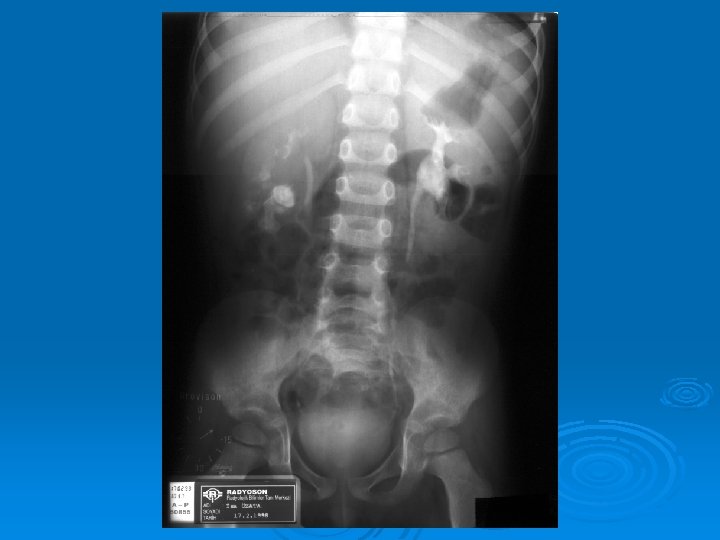

Çocukluk Çağında İdrar Yolu Enfeksiyonları İZLEMDE GÖRÜNTÜLEME GEREKEN HASTALAR Akut pyelonefrit (tüm yaş grupları) 1 yaş altı çocukta bakteriüri Erkek çocukta tekrarlayan sistit İYE ve hipertansiyon Doğuştan orta hat anormalliği

Çocukluk Çağında İdrar Yolu Enfeksiyonları İZLEMDE TANISAL GÖRÜNTÜLEME YÖNTEMLERİ Ø Miksiyon sistoüretrografisi: Vezikoüreteral geri kaçış (VÜR) görüntülenir. Ø DMSA sintigrafisi: Skar görüntülenir. Ø IVP: Tıkanıklık görüntülenir. Ø DTPA sintigrafisi: Tıkanıklık, böbrek fonksiyonları bozuk hastalarda atılım fonksiyonlarını değerlendirilebilir.